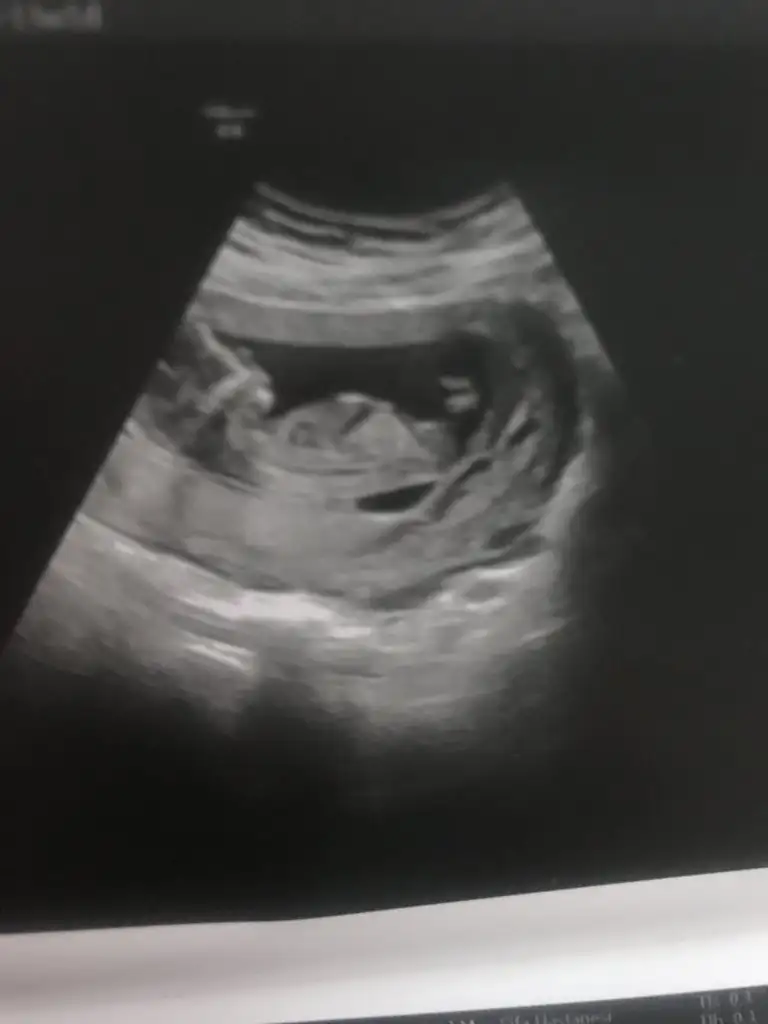

Nubu göremiyorum görüntü olarak kıza benzettim varsa 11 hafta paylaşın netleştirim kızmı erkekmiEki Görüntüle 2307451 Merhabalar vizede yorum yapar mısınız 12 hafta 6 günlük doktora sordum belli değil soldaysa kız sağdaysa erkek diyorlar dedi dalga geçer gibi

Sağa yakın kız gibi sanki